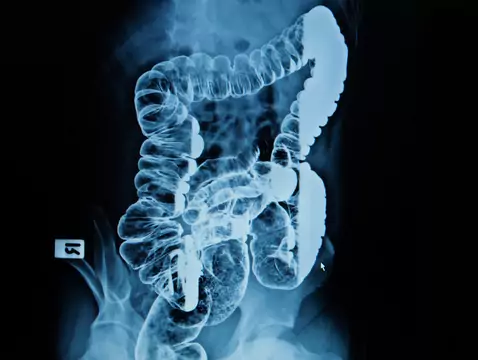

El cáncer colorrectal es una neoplasia que se produce en: el colon, la flexura sigmoidea y el recto. En el 90-95% de los casos la incidencia del cáncer colorrectal es esporádica, en el 5-10% restante...